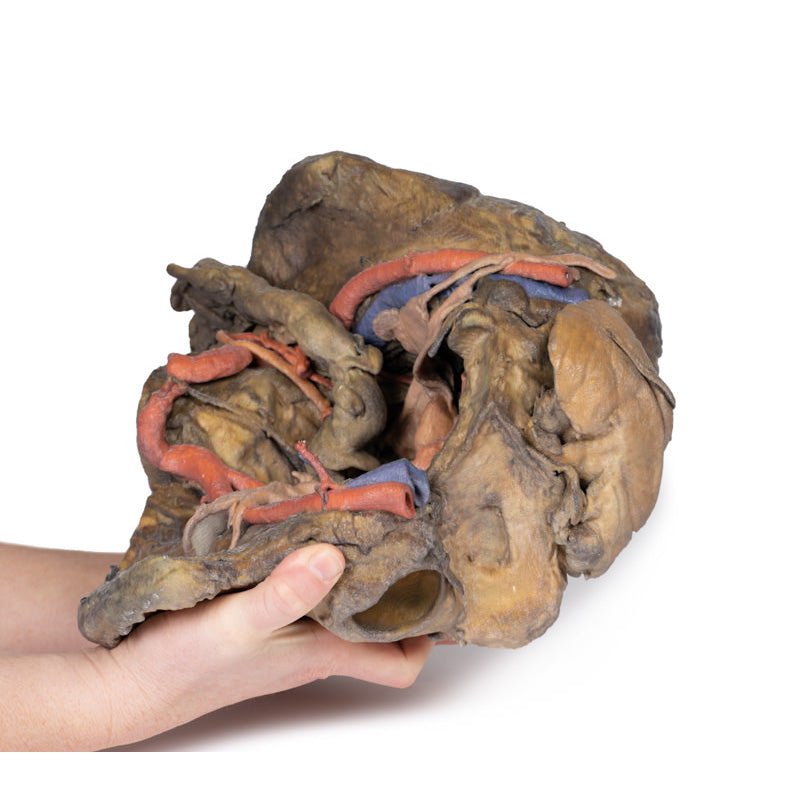

This 3D model presents a deep dissection and isolation of the pelvis from surrounding regions, particularly

demonstrating visceral and neurovascular structures relative to deep ligaments and osseous features.

On the right side of the preserved pelvis, the entire femur and thigh musculature has been removed to

demonstrate the obturator membrane, the articular cartilage of the acetabulum and the transverse ligament of the

acetabulum. Posteriorly the entire gluteal region has been dissected to expose the superior gluteal foramen and

the origin of the superior gluteal artery. The sacrotuberous ligament has been removed to demonstrate the

sacrospinous ligament, with some branches of the inferior rectal artery retained within the exposed ischoanal

fossa.